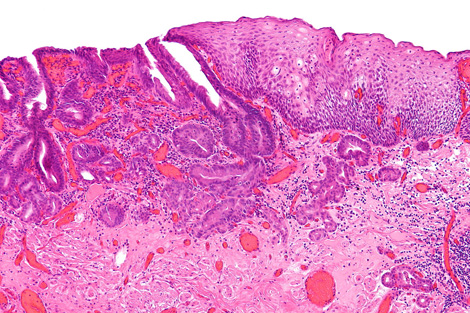

A team led by biophysicist Peter Weightman uses the ALICE accelerator at England’s Daresbury Lab to image the biochemical composition of tissue from patients afflicted by a condition called Barrett’s esophagus. Barrett’s sufferers are 10 times more likely to develop esophageal cancer, but most acquire symptoms too late for treatment.

With ALICE-created images, doctors can distinguish pre-cancerous tissues from benign ones. The method may one day give diagnoses in time to save lives.

Doctors currently diagnose pre-cancerous tissues in patients with Barrett’s esophagus by analyzing random cell samples. This technique can miss areas with telltale changes, says University of Liverpool gastroenterologist Mark Pritchard, who works on Weightman’s team. If the new technology is shown to be accurate and reliable, it could give doctors a more comprehensive view.

To measure cancer cues, scientists tune the ALICE accelerator’s infrared light to a wavelength that excites one specific type of cellular component, such as DNA or proteins. When the light shines into the sample, the excited electrons from that component lose their energy in the form of photons—light researchers can see. They collect this reflected light with a micron-wide tube that they spend about an hour scanning slowly over the entire tissue surface. The result is a map of the density of one component, such as DNA, across the sample.

For each sample, the researchers repeat the process to map three or four different components known to vary in cancerous versus noncancerous tissues. “When you go cancerous, the DNA goes up and the protein goes down,” Weightman says. That’s because cancer cells have more active DNA than healthy ones, facilitating the cell growth and DNA duplication necessary for a tumor to form.